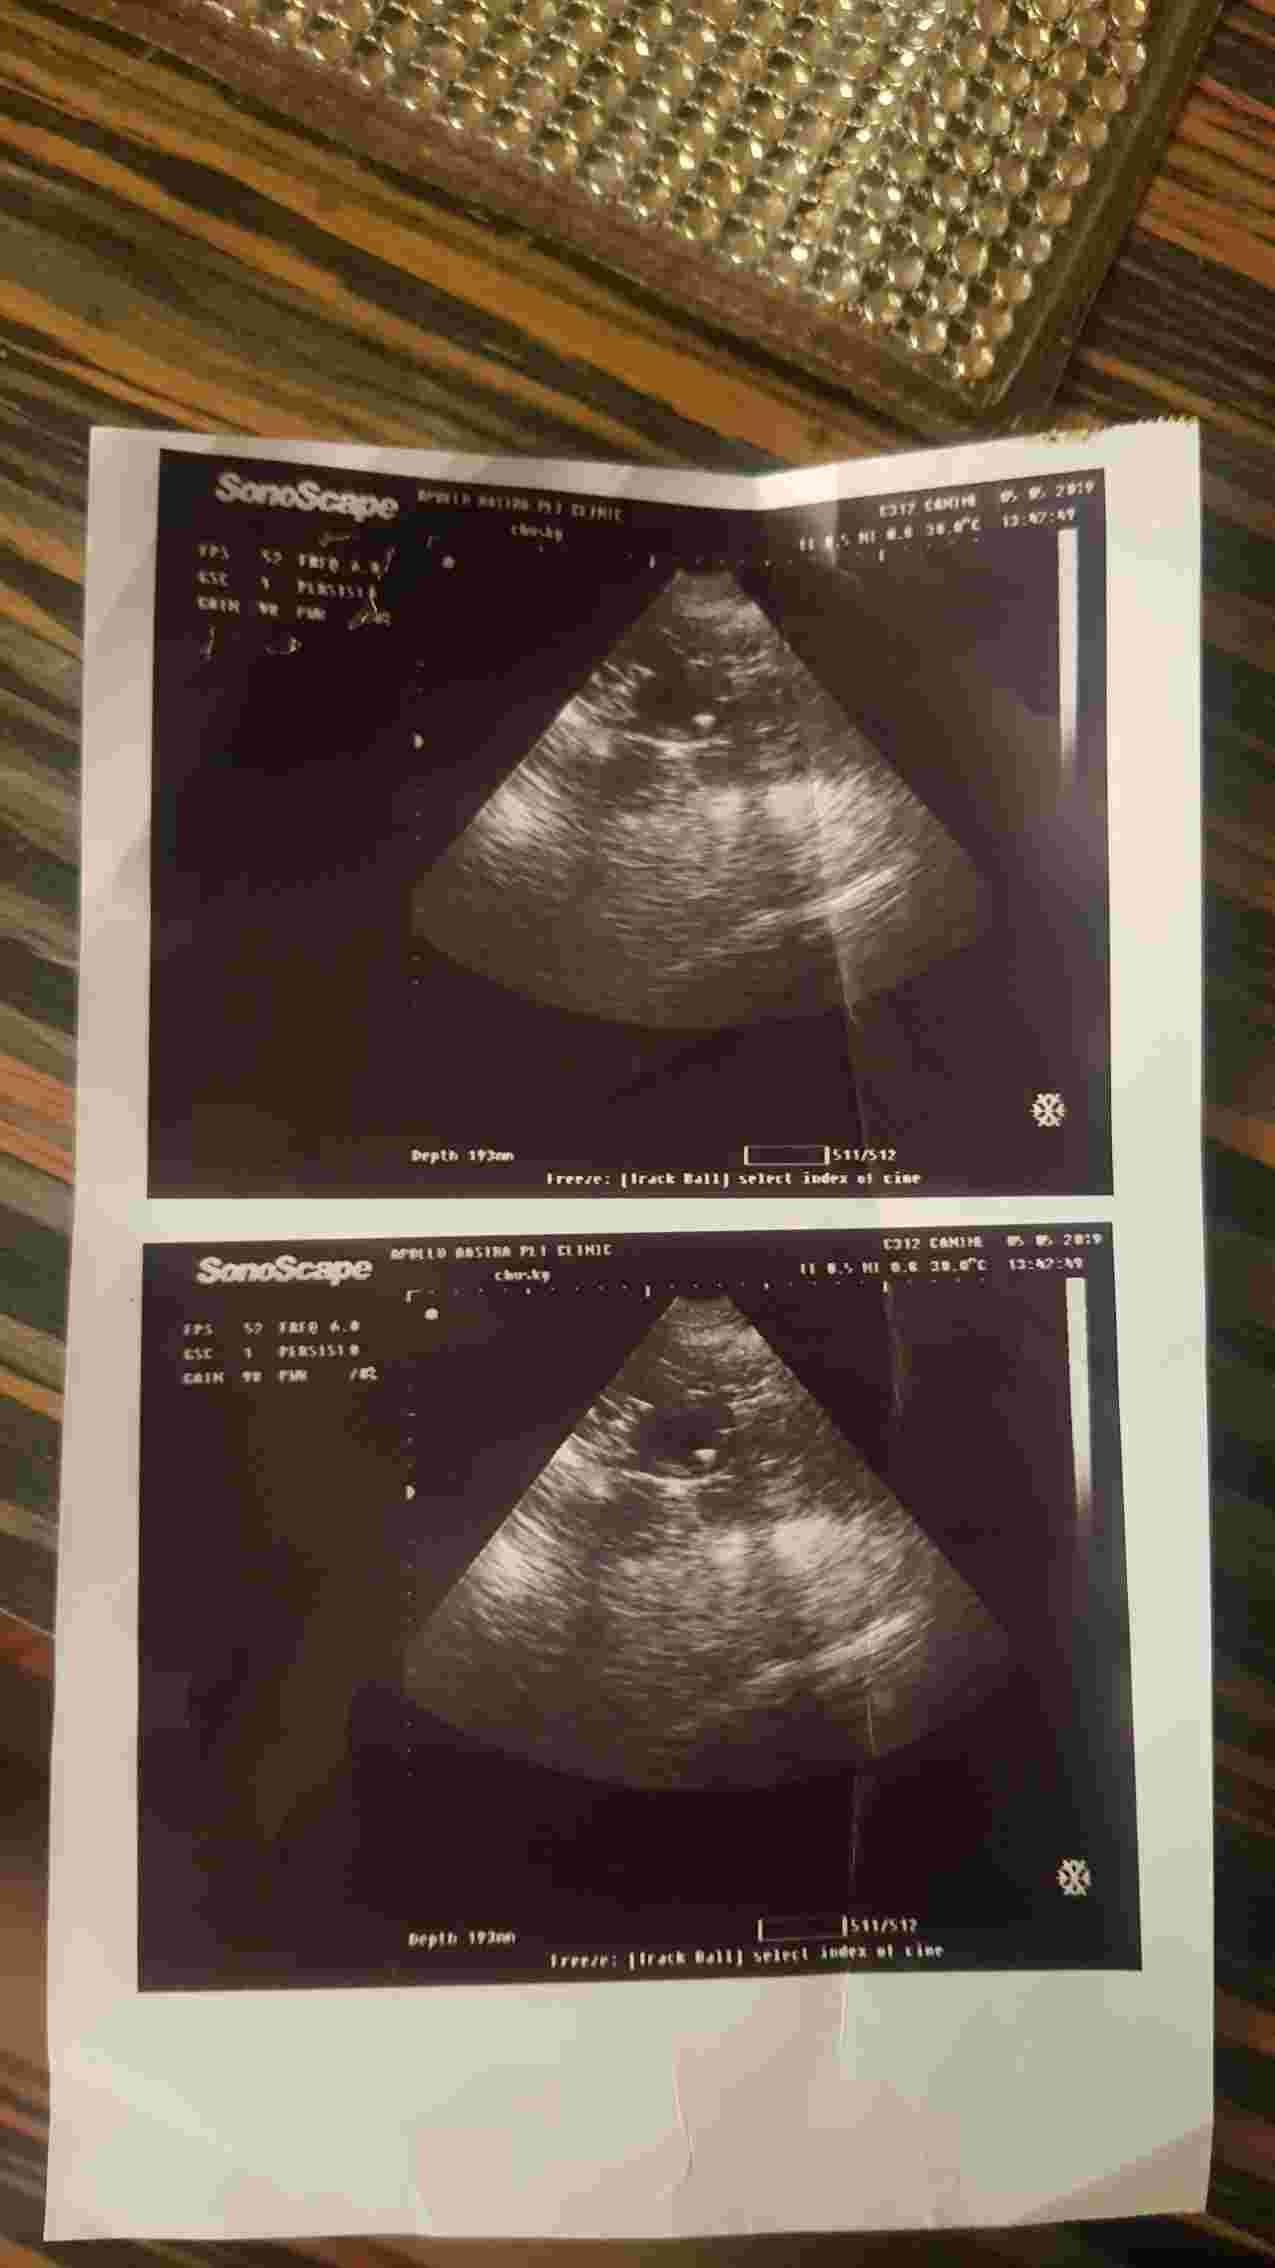

Hi,my dog is over weight and she is behaving unusual for some months.She is sleeping too much, doesn't want to stand.I took her to my vet and he told me that my dog have a pus in her uterus and it's just at an early stage.he given me medicines to give her,at first she was recovering but then some days later she started to do brown vomit and black stool so i stopped giving those medicines but now her lower stomach have grown larger is very much hanging. Below is her ultrasound pic about month ago

Hello. The pus in her uterus is a very serious condition called pyometra. Usually, the best way to deal with this is to perform an ovariohysterectomy & spay her. The only time to consider treating this condition with medications is if Chuski is a valuable breeding animal. But you are risking her health & she could die from this. Please consider the surgery. Most dogs do very well if it is done before they get too sick. I hope she is feeling better soon. Thanks for using Petco Pet Education Center, formerly Petcoach.